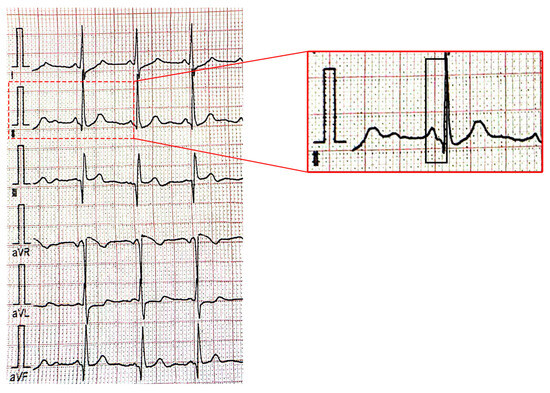

Figure 2 and Figure 3 present supraventricular ectopic beats in a neonate with TS and electrocardiographic changes (short PR interval) in a 2–years–old patient with TS.

Figure 3.

Electrocardiogram showing a short PR interval (80 milliseconds) (black rectangular shape) in a 2–year–old patient with tuberous sclerosis: first figure showing peripheral derivations of the ECG leads and second figure showing the magnified DII peripheral lead.